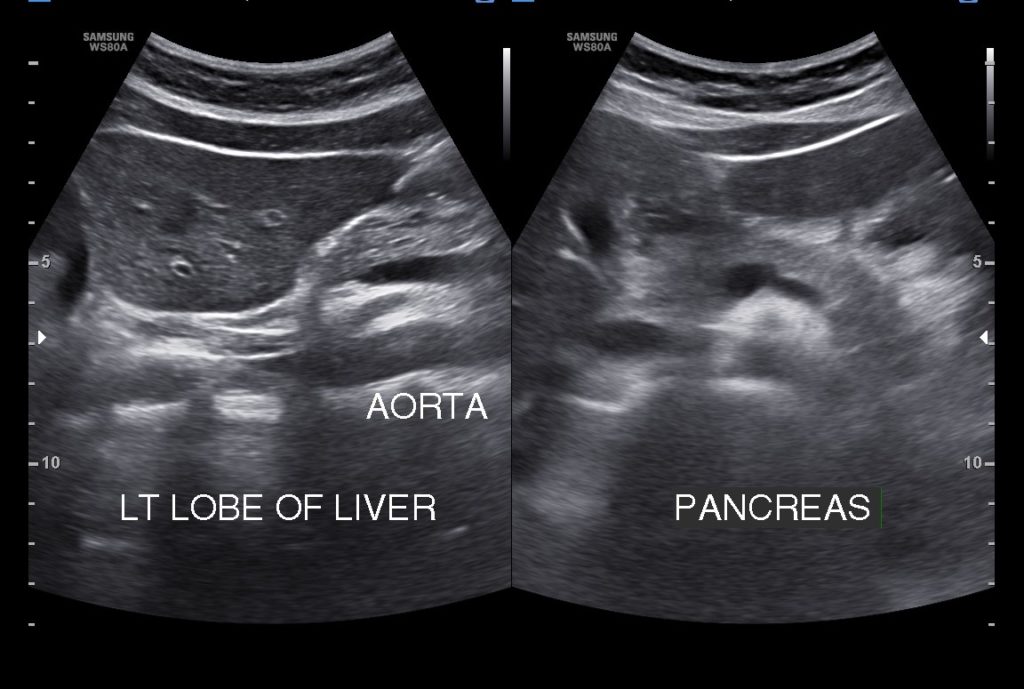

UPPER ABDOMEN –LIVER, GALL BLADDER, PANCREAS, SPLEEN, KIDNEYS & PARA-AORTIC REGIONS